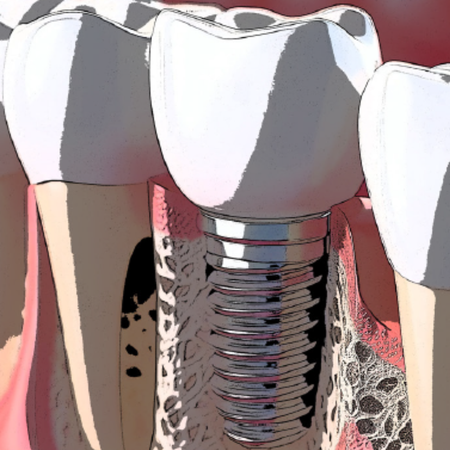

OBJETIVO: Esta revisão sistemática com meta-análise teve o propósito de comparar a reabsorção óssea peri-implantar pós-cirúrgica entre duas técnicas de fresagem durante a instalação de implantes dentários: fresagem de baixa velocidade sem irrigação e fresagem de alta velocidade com irrigação. MATERIAL E MÉTODOS: Foram conduzidas buscas eletrônicas nas bases de dados PubMed, Web of Science, BVS e EMBASE para publicações até 2024. Foram incluídos ensaios clínicos...

OBJECTIVE: This systematic review with meta-analysis purpose to compare post-surgical peri-implant bone resorption between two drilling techniques during dental implant installation: low-speed drilling without irrigation and high-speed drilling with irrigation. MATERIAL AND METHODS: Electronic searches PubMed, Web of Science, BVS and EMBASE databases were conducted for publications up to 2024. Randomized clinical trials with data from patients that received dental implant installation and...